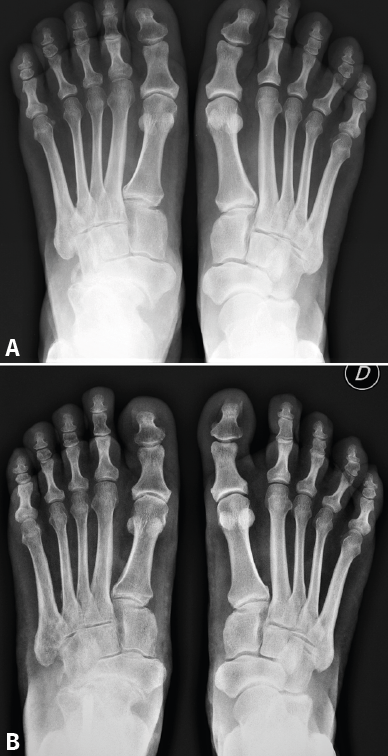

Introducción y objetivos: la enfermedad de Müller-Weiss (EMW) es una patología causada por la displasia del navicular que, en muchos casos, está mal o infradiagnosticada. Se presenta como un “pie plano-varo paradójico” y una artropatía talonavicular. En este trabajo pretendemos explicar nuestra experiencia con una cirugía de preservación articular –osteotomía “supervalguizante” de calcáneo aislada (de tipo Dwyer con desplazamiento lateral)– en nuestra primera serie de pacientes a los que no se realizó una artrodesis.

Material y métodos: estudio descriptivo retrospectivo de una serie de 17 casos de EMW en 15 pacientes operados en nuestra Unidad de Pie y Tobillo (2007-2015). Analizamos diferentes parámetros a través de la historia clínica, la exploración física, el estudio radiológico y escalas de valoración estandarizadas (escala visual analógica –EVA–, American Orthopaedic Foot and Ankle Society –AOFAS– y Likert).

Resultados: todos los pacientes tenían un varo subtalar y el 88,2% una fórmula metatarsal index minus. Existió una mejoría en todas las escalas de valoración utilizadas y en los parámetros radiológicos estudiados (cobertura talonavicular y clasificación de Maceira) en la mayoría de los pacientes. No se registraron complicaciones importantes. Un paciente no mejoró y precisó de una artrodesis a los 4 años de la osteotomía.

Conclusiones: la EMW produce un pie plano paradójico. La corrección quirúrgica del varo subtalar permite una mejoría clínica y radiológica notable. La osteotomía “supervalguizante” es una técnica sencilla y se ha constituido en nuestra técnica de elección, independientemente del estadio radiológico. La artrodesis de la columna medial ha quedado como técnica de rescate para fracasos de la cirugía de preservación articular.

Introduction and objectives: Müller-Weiss disease (MWD), a tarsal navicular dysplasia, is often misdiagnosed or underdiagnosed. Clinical presentation as a paradoxical “flatfoot varus” combines with arthritic talonavicular changes. In the present study we show our experience with a joint-preserving surgical treatment –isolated “super-lateral-slide osteotomy”– in the first series of patients in which a tarsal arthrodesis was not performed.

Material and methods: we present a descriptive, retrospective study of a series of 17 MWD cases in 15 patients that underwent surgery in our Orthopaedic Foot and Ankle Unit (2007-2015). We analyze different parameters through the clinical history, physical examination, complementary tests and standardized evaluation scales (visual analogue scale –VAS–, American Orthopaedic Foot and Ankle Society –AOFAS–, and Likert).

Results: all patients presented with subtalar varus and 88.2% had a metatarsal index minus formula. There was an improvement in all scales studied. Radiographic parameters also improved in all cases (talonavicular coverage, Maceira classification). Most patients had considerable pain relief and just one did not improve and required an arthrodesis four years after the osteotomy.

Conclusion: MWD presents with a paradoxical flatfoot varus. Surgical correction of hindfoot varus allows for a mechanical change that produces clinical and radiological improvement. An isolated “super-lateral-slide osteotomy” is an easy technique to achieve varus correction regardless the radiographic stage of the disease and has become our surgical procedure of choice. Medial column arthrodesis is left as a salvage procedure for those cases that do not improve with the osteotomy.